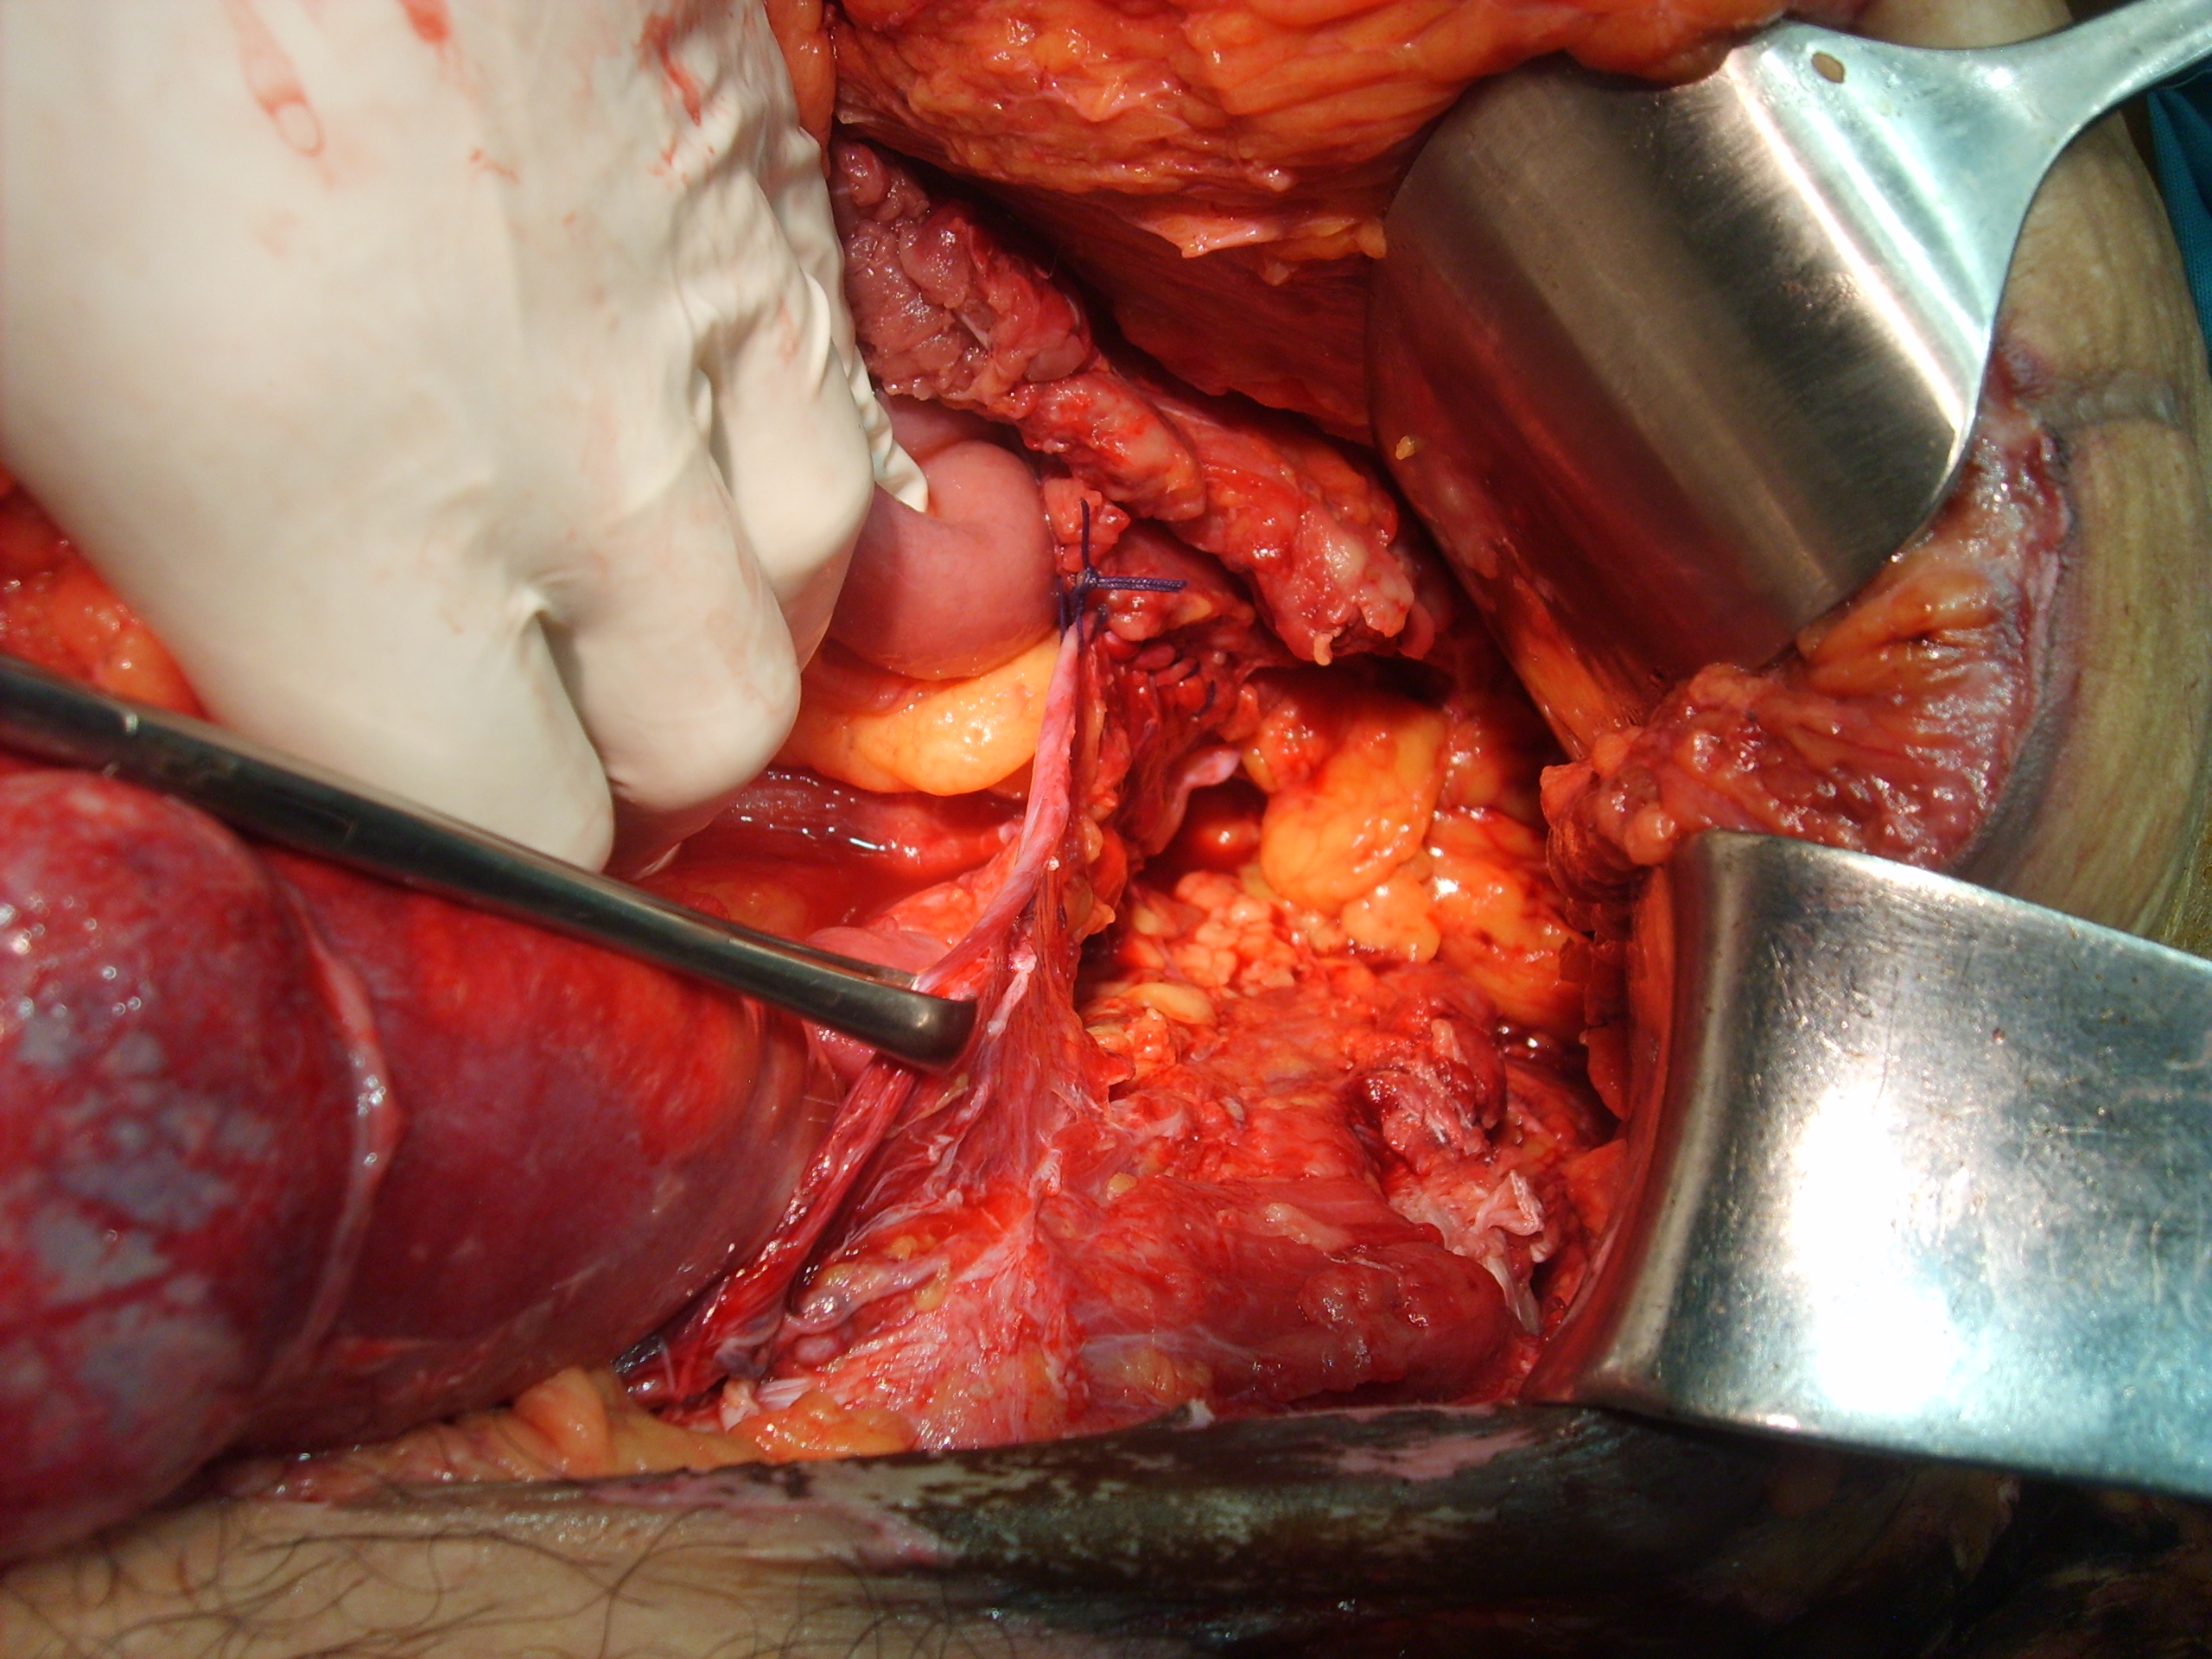

Luego de estabilizada la paciente y al cuarto día de la cirugía del abdomen abierto se lleva la paciente al quirófano. Se constata abdomen con escaso liquido serohemático y asas intestinales sin compromiso vascular por lo que se decide cerrar el abdomen. Es dificultosa la tarea de contener las asas intestinales en la cavidad abdominal debido a la ausencia de pared lateral. Se decide el decolamiento del colon derecho e izquierdo a fin de lograr un espacio para colocar la prótesis, es decir generar un espacio real con el peritoneo para introducir la malla. La sugerencia adecuada del Dr Zorraquino es imposible de realizar, la enferma presenta una retracción importante de los músculos rectos que determinan una cavidad abdominal que supera ampliamente los 900 cm². Se coloca dos mallas de proceed 30 x 30 intraperitoneal fijadas con puntos al espesos total de los remanentes musculares y sobre la misma una malla de prolene 30 x 30 fijada abajo al pubis y a ambas crestas ilíacas y por arriba al plano aponeurótico de los rectos y Oblicuo mayor. Se deja piel y celular abierto. Vuelve a Cuidados Intensivos.

Interesantísimo caso el que nos presenta el Dr. Carlos Cano, bien iconografíado. Se ve en la última foto o así lo interpreto la sección de los músculos rectos y oblicuos.

Estimado Dr Carbonell, aprecio su valioso comentario. No hubo escape de contenido intestinal. Se decide el abdomen abierto por la lesión de la serosa del sigmoides y por acidosis intraoperatoria que presentó la paciente. La enferma ingresa a la Unidad de cuidados intensivos en grave estado. La evaluación de la enferma nos plantea en primer lugar y por el tiempo transcurrido una imposibilidad de reconstrucción anatómica de la pared abdominal por retracción muscular por lo que la separación de componentes estaría descartada. Evalúo la posibilidad de colocar dos mallas separadoras de tejido de 30 x 30 intraperitoneal ya que la superficie a cubrir es extensa, y luego colocar sobre esta y fijada al plano aponeurótico de los músculos anchos y rectos seccionados una malla de polipropileno. Gracias.

Estimado Dr Reyes, aprecio tus comentarios, nosotros no disponemos de mallas biológicas, que si creo hubiesen sido de utilidad en este caso.Con respecto a colocar malla de polipropileno sobre la proceed, fué para tratar de darle más contención al contenido abdominal, por eso esa prótesis la fijamos al pubis y a las crestas ilíacas que estaban totalmente a la vista, según mostramos en algunas fotos.